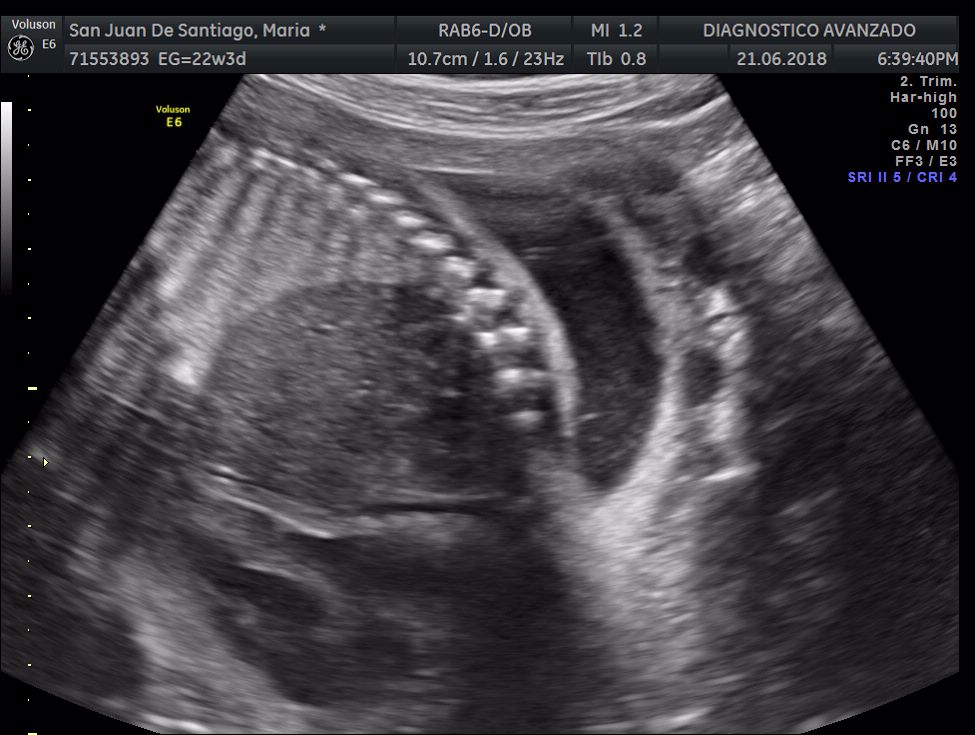

¡Hola a todos! Hoy hemos ido a hacer la tradicional ecografía 3D de la niña, os dejamos todo el material (aunque es un poco demasiado).